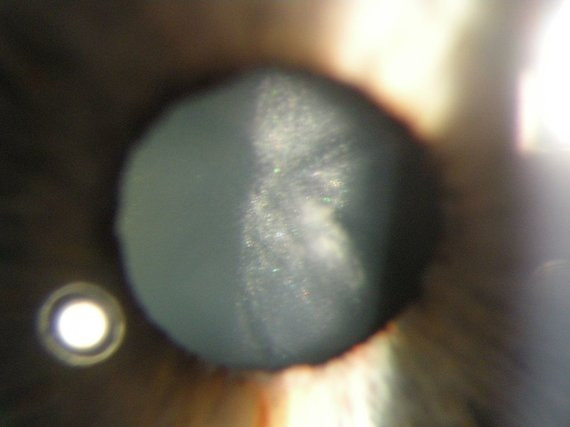

Katarakta – viena dažniausių aklumo priežasčių

Katarakta – tai akies lęšiuko sudrumstėjimas. Tai – viena dažniausių aklumo priežasčių pasaulyje (46 proc. atvejų, Pasaulinės sveikatos organizacijos duomenimis).

Kataraktų yra įvairių – neretai – labai gražių, akies lęšiukas primena kosmosą ar žvaigždyną. Žinoma, toks vaizdas matomas žvelgiant iš arti į pažeistą akį, o pats pacientas pradeda matyti it „per rūką“. Ir tas „rūkas“ stiprėja.

Iki šiol nėra žinoma, kaip sustabdyti kataratos susiformavimą ar progresavimą. Labai didelė tikimybė, kad kataraktą turėsime visi, tik ne visi spės išsioperuoti. „Vienintelis kelias spręsti šią problemą – operacija. Išoperavus kataraktą ta pačia operacija galima pagydyti ir trumparegystę, ir toliaregystę ar astigmatizmą. Šiandien kataraktos operacijos metu daroma maždaug 1,8-2 mm pjūvis. Lęšis yra nebe kietas, o „minkštas”. Įdėtas į akį jis „išsilanksto“, išsiskleidžia kaip gėlės žiedas. Kataraktos operacija trunka apie 15 minučių, kai kurie medikai spėja ją užbaigti ir per 7 minutes. Žmogus tą pačią dieną išleidžiamas gydytis namuose, gali parvykęs žiūrėti televizorių. Aišku, kurį laiką tenka lašintis priešuždegiminius vaistus.

Kataraktos operacijos galima pasekmė – ragenos endotelio dekompensacija. Dėl šios priežasties ragena pradeda burkti, akį pradeda skaudėti, ženkliai pablogėja matymas. Dėl to gali prireikti daryti ragenos transplantaciją. Laimei, dėl ištobulėjusios technikos tokių operacijų tenka daryti vis mažiau.